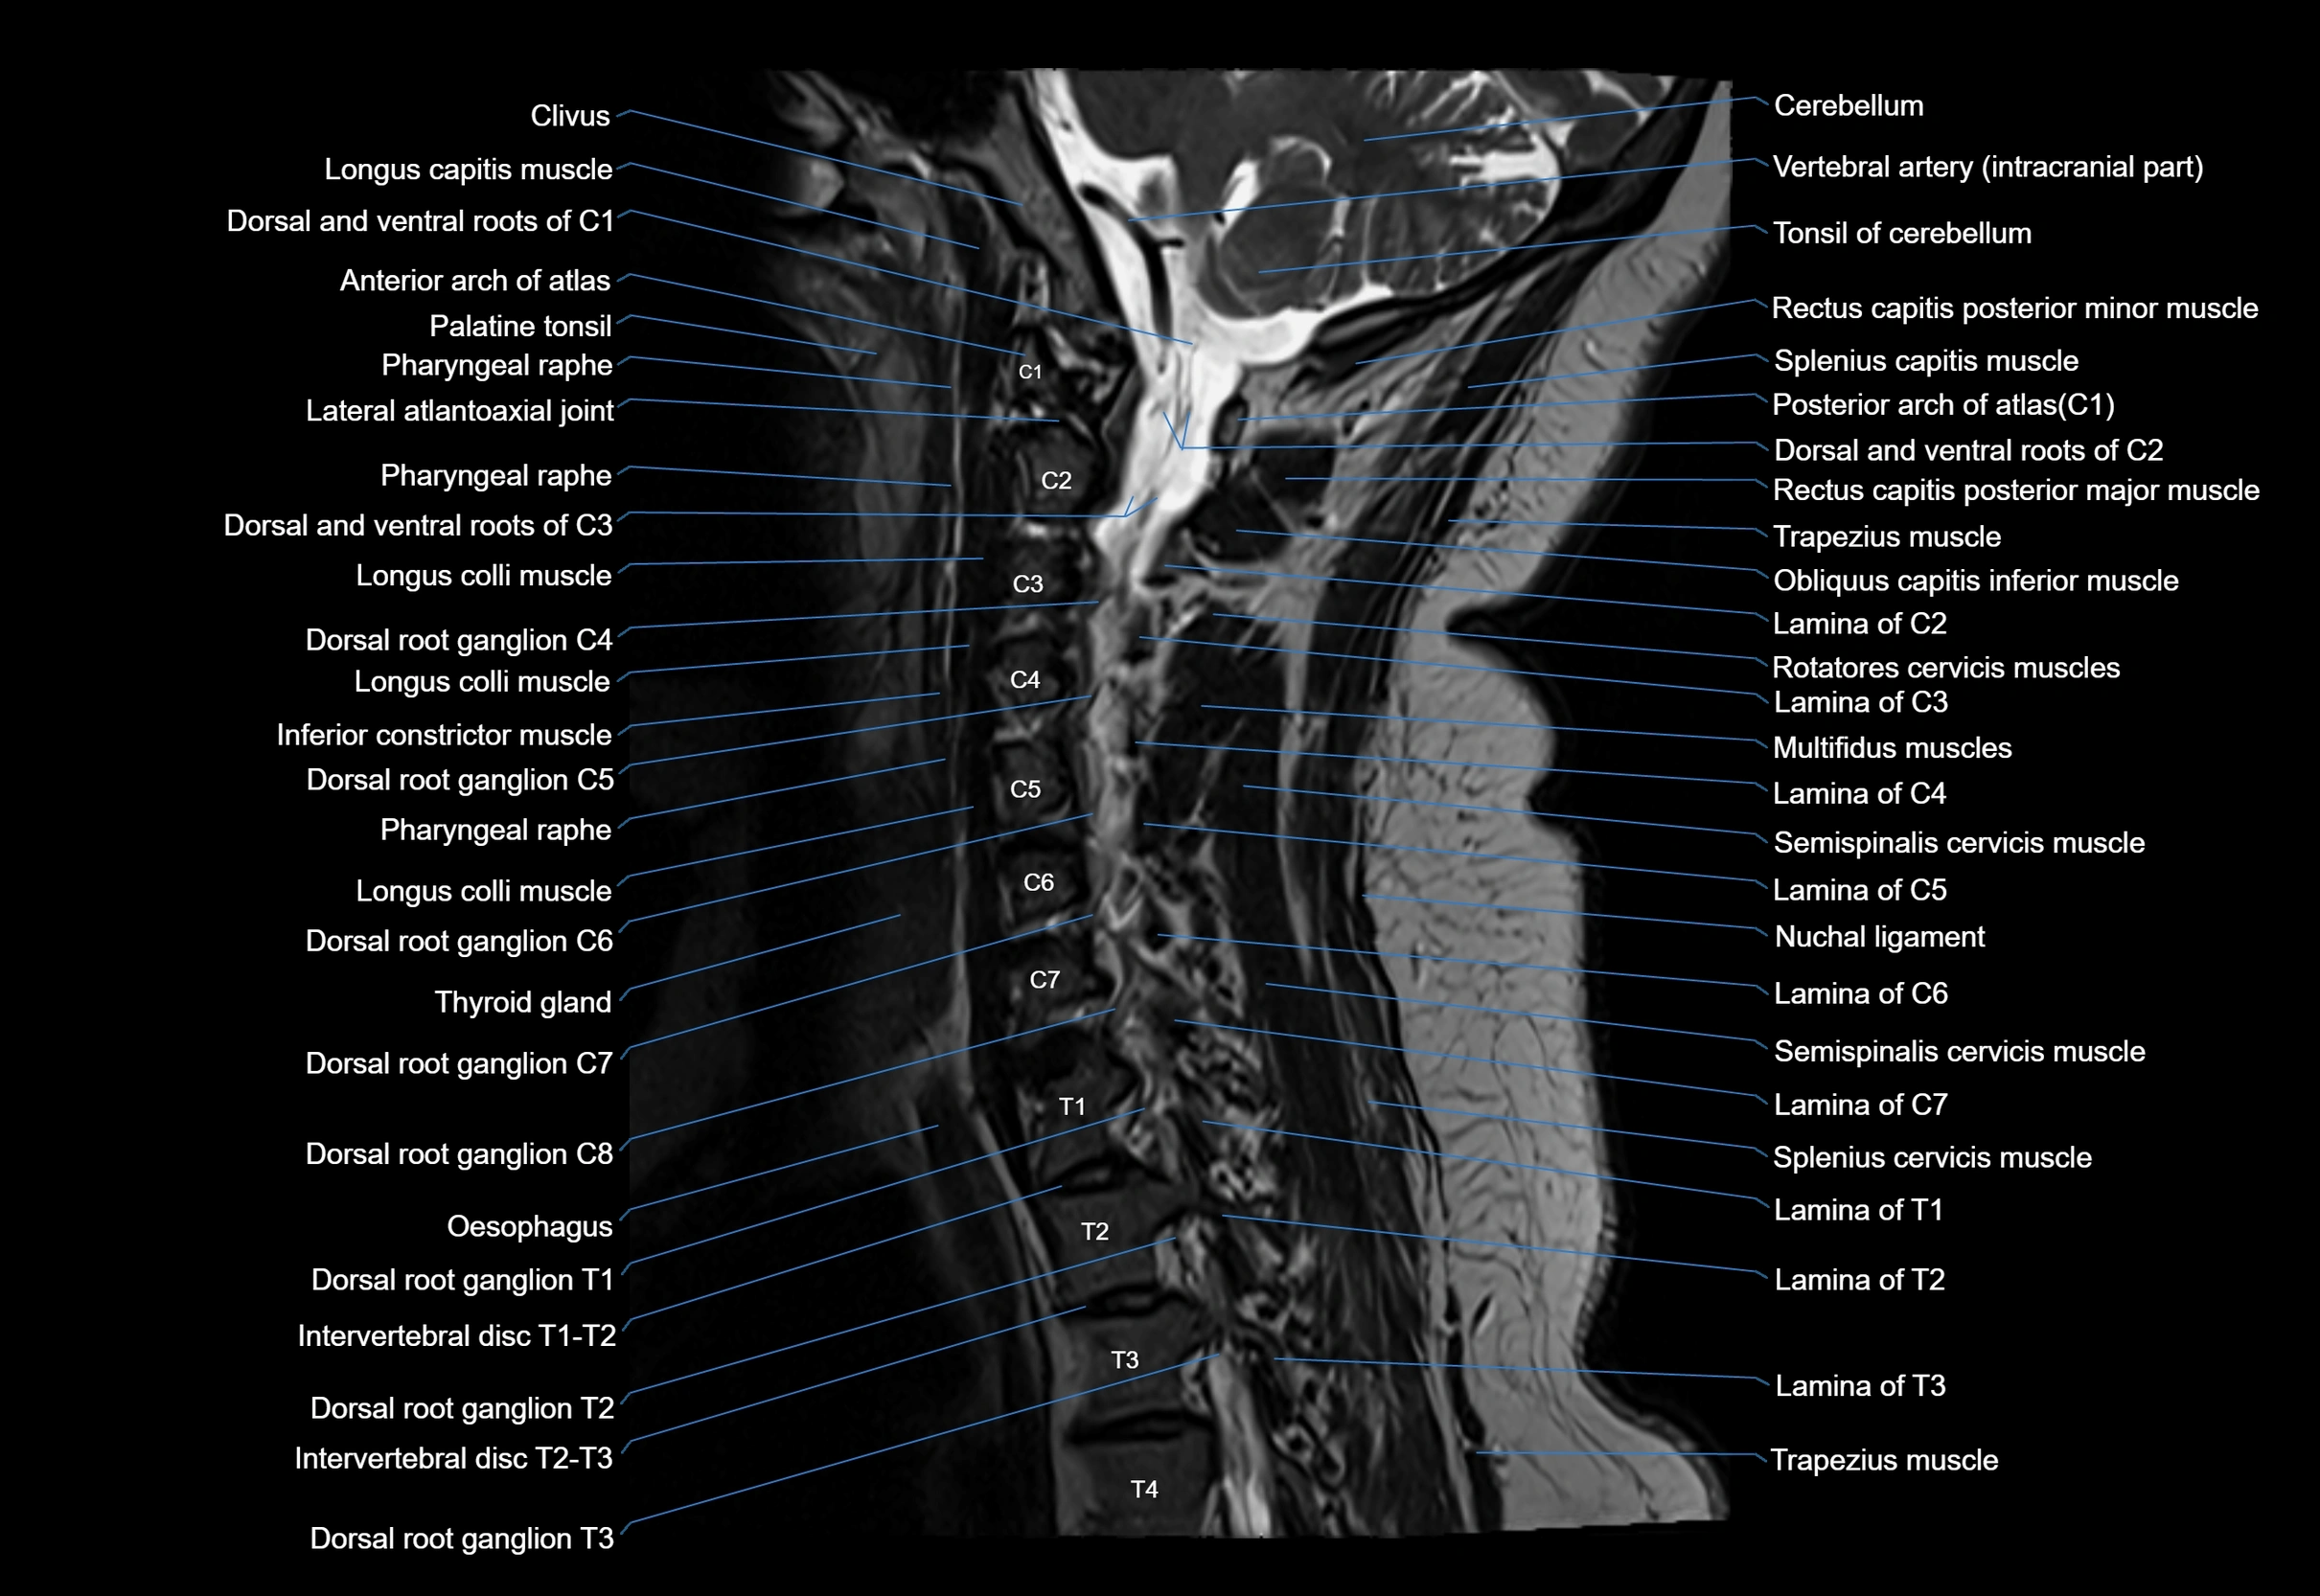

MRI appearance

T1-weighted images:

• Annular epiphysis: Low signal cortical rim at the vertebral margin

• Adjacent marrow: Intermediate-to-high signal in the vertebral body

• Disc interface: Clear delineation between bone and annulus

T2-weighted images:

• Annular epiphysis: Low signal intensity line

• Endplate cartilage (in younger patients): Intermediate signal

• Intervertebral disc: High signal nucleus pulposus

STIR:

• Annular epiphysis: Low signal cortical rim

• Adjacent marrow: Suppressed fat signal with preserved bony outline

• Utility: Highlights marrow and endplate interface in developing spine

MRI image

image